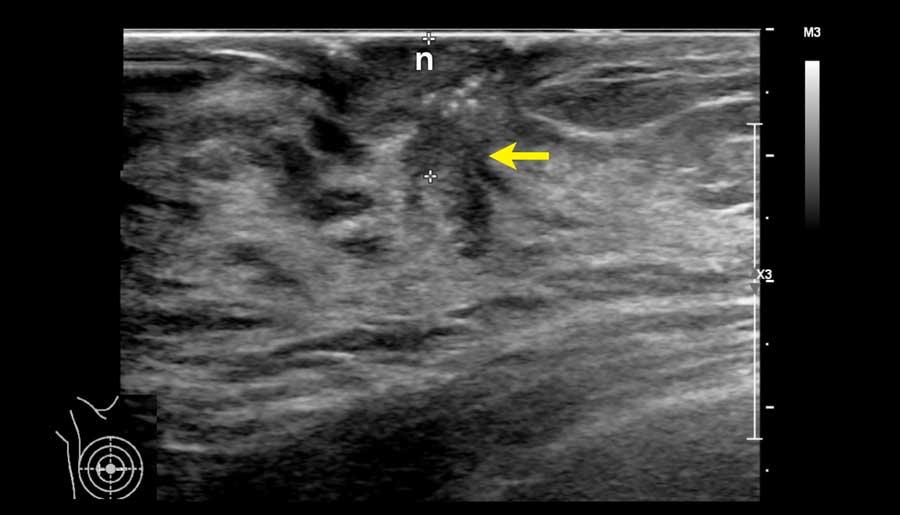

Đây là một khối u khác phía sau núm vú (n).

Các khối u này có thể rất khó phát hiện.

Ở mọi phụ nữ có triệu chứng núm vú tụt vào trong, vùng này cần được khảo sát cẩn thận.